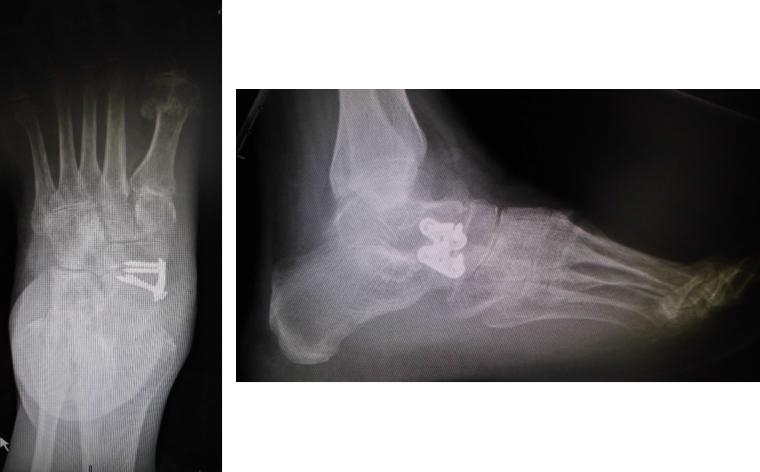

Per quanto riguarda le articolazioni del mesopiede e del retropiede, l’interessamento artritico, se in fase avanzata, viene trattato con artrodesi allo scopo di dare allineamento e stabilità, togliendo al contempo il dolore.

Quando ad essere interessato è il primo raggio, con presenza di gravi erosioni articolari, l’artrodesi della MF1 rappresenta certamente una tecnica sicura e affidabile, che permette il persistere della correzione nel tempo, toglie il dolore e conferisce stabilità.